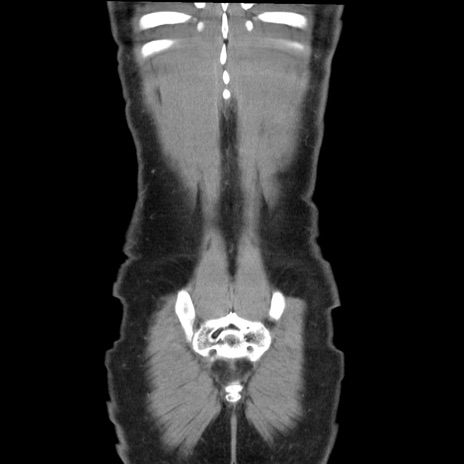

症例36(冠状断像)

【症例】20歳代 男性

【主訴】心窩部痛

【現病歴】今朝より上腹部痛あり。一旦軽快していたが再度出現したため救急要請。昨日夕に白身の魚を含む刺身を食べた。

【身体所見】BP 136/89mmHg、HR 74/min、BT 37.0℃、腹部:膨満、軟、心窩部に圧痛あり。反跳痛なし、筋性防御なし、腸雑音やや亢進あり。

【データ】WBC 17700、CRP 0.48